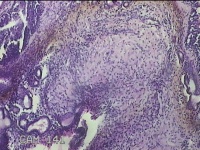

右侧鼻腔新生物

性别

女

年龄

31岁

临床诊断

1.鼻息肉 2.变应性鼻炎

一般病史

反复鼻塞、流涕嗅觉减退1年。

标本名称

大体所见

灰白暗红色不规则碎组织1.5x0.7x0.3cm一块,表面糜烂,内有少许骨质。